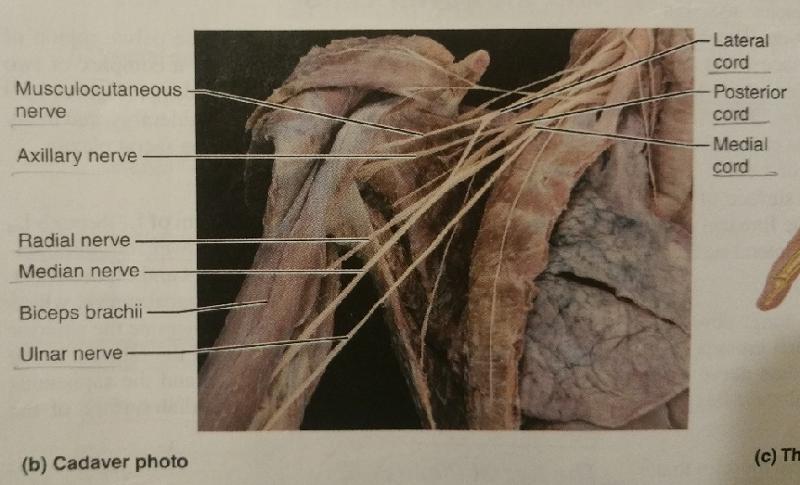

The brachial plexus after being rearranged consecutively into trunks, divisions, and cords, finally becomes subdivided into what 5 major peripheral nerves?

1. axillary nerve

2. radial nerve

3. median nerve

4. musculocutaneous nerve

5. ulnar nerve

Identify the blanks.